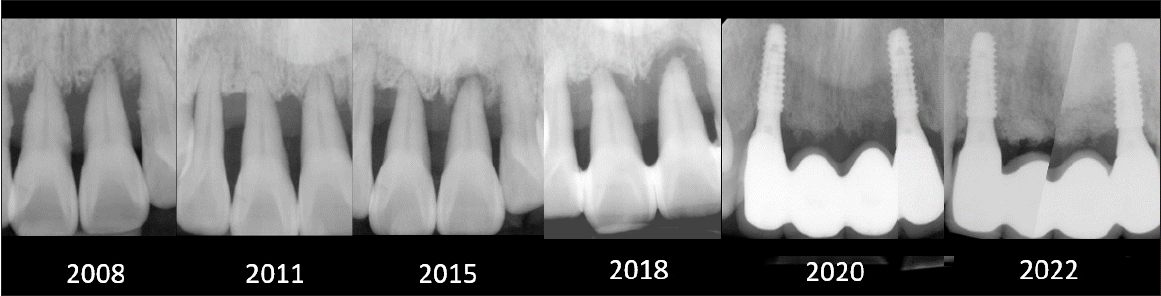

Figure 3.

Full-mouth periapical radiograph at baseline (2008), showing generalized severe alveolar bone loss and advanced periodontal destruction